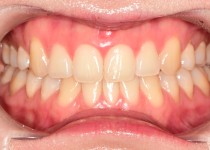

만 52세 전악 상악, 하악 전체 임플란트…

만 56세 상 하악 임플란트 증례